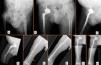

Fractura extracapsular del fémur proximal (AO/OTA 31-A)Quince pacientes sufrieron una fractura extracapsular de fémur proximal (5 31-A1, 9 31-A2 y uno 31-A3). La fijación extramedular fue la elección en 4 pacientes, ya fuera por observar preoperatoriamente un canal estrecho o por la presencia de un implante previo que imposibilitaba el enclavado. En todos ellos se utilizó una placa con tornillo deslizante de cadera, y en todos el implante estaba sobredimensionado con respecto al tamaño del hueso. Las principales complicaciones intraoperatorias registradas fueron la necesidad de un tornillo cefálico muy corto (55mm), la protrusión del tornillo cefálico y la incapacidad para retirar material de osteosíntesis previo (fig. 2 A-F).

Fractura pertrocantérea (A, B). Los problemas observados fueron: deformidad secundaria a osteotomía del fémur proximal (B, I), presencia de un implante (A, B), osteotomía supracondilar (G), osteoporosis (A), hueso pequeño (observar sobredimensión del implante) (C, D, H, I). Fractura posterior supracondílea (G-I).

De los 11 pacientes tratados mediante un implante intramedular, en 4 se usaron clavos de Ender y en los 7 restantes, clavos intramedulares. La fractura 31-A3 fue fijada con un clavo intramedular largo tras la retirada de un clavo supracondilar corto implantado por una fractura supracondílea previa. No hemos recogido complicaciones intraoperatorias en el grupo de enclavado endomedular, si bien sí se han apreciado implantes ligeramente sobredimensionados.